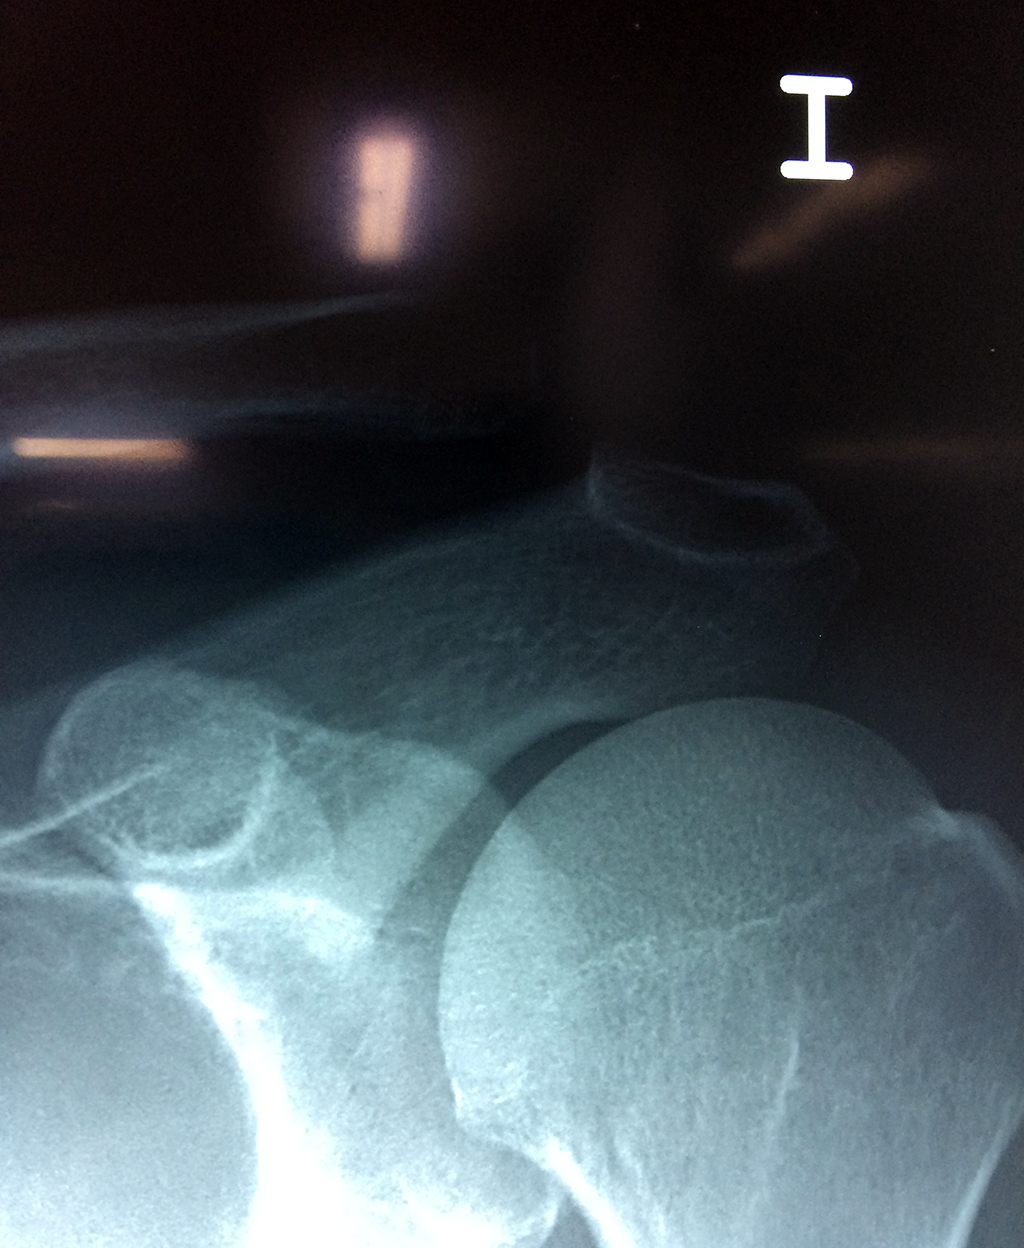

Cirugías de Calcaneo - Clavícula